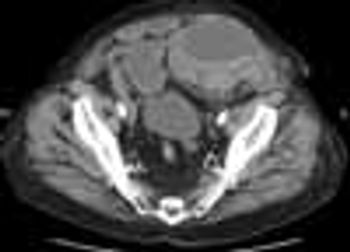

Five days after starting aspirin and warfarin with an enoxaparin bridge for new-onset atrial fibrillation, a 92-year-old man presented with abdominal pain, nausea, and vomiting. The patient appeared ill and was tachycardic. He had dry mucous membranes; pale sclerae; diminished bowel sounds; and a large, tender left lower abdominal mass. Hematocrit was 22% (baseline, 39%); hemoglobin, 6.8 g/dL; blood urea nitrogen, 65 mg/dL; and creatinine, 3.2 mg/dL (baseline, 1.3 mg/dL). His "pre-renal" ratio was 20. These findings were consistent with bleeding and acute renal failure. He also had a supratherapeutic international normalized ratio (INR) of 4.1.